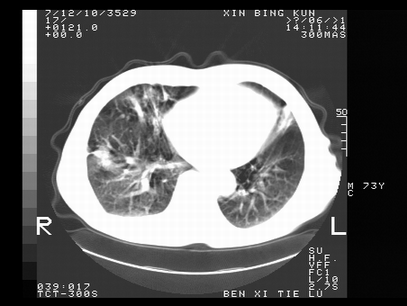

标题: CT10820:男,73岁,病史肺TB,现病史肺炎,直肠CA术后 [打印本页]

标题: CT10820:男,73岁,病史肺TB,现病史肺炎,直肠CA术后

双肺间质改变,依据病史双肺多发结节灶考虑转移,少量胸水.

1.两肺结核.2.两肺多发转移瘤.3右侧少量胸腔积液4.主动脉钙化.

双肺多发结节及条片状致密影,右侧少量胸腔积液。临床:直肠ca术后,肺tb病史。综合考虑:1 双肺转移!2 继发性肺结核合并感染!

此人病史较复杂,原有肺结核,直肠癌术后。肺部病灶形态亦呈多形性。因此,不可仅以一种病来解释肺部的病变。双肺多发的类圆形结节灶,结合病史还是首先考虑转移瘤,而双肺其余病灶还需结合化验室检查,结核或肺部感染在无其它检查资料的情况下不好排除。还是那句话----放射科医生不是开照像馆的,我们也是医生,看片一定要多结合临床及其它检查资料。要当一名合格的放射科医生,并不比当一名临床医生容易,我们可别把自已不当医生看。

两肺多发结节影,并见滋养动脉与其相连,考虑 两肺转移. 右侧胸腔积液考虑胸膜转移.

左肺上叶下叶背段,右肺中下叶见多发斑片状、条索状高密度影,兵变周围小结节影形成“树芽”样改变。 左肺上叶舌段近前胸壁处及右肺中叶内侧段见结节影。右侧胸膜腔内见液体密度区。纵隔内未见明确增大淋巴结。考虑左肺上叶舌段近前胸壁处及右肺中叶转移瘤可能性大。两肺继发型肺结核。右侧胸腔积液。

还有心包少量积液。